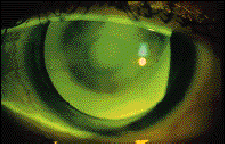

FIG. 2: Concentric design with slight lag.